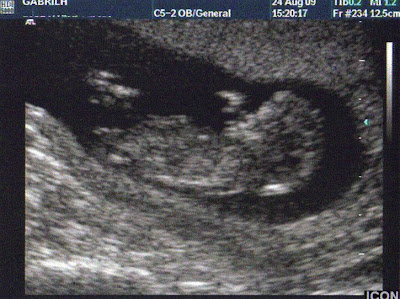

Σήμερα το μεσημέρι, ούσα έγκυος 12 εβδομάδων και 1 ημέρας, πήρα τον άντρα μου και την κοιλιά μου και πήγαμε να κάνουμε τον πρώτο μας υπέρηχο! Πρόκειται για τον υπέρηχο αυχενικής διαφάνειας, ο οποίος αποτελεί κομμάτι του προγεννητικού ελέγχου και γίνεται ανάμεσα στην 11η και 13η εβδομάδα. Σκοπός του είναι να εκτιμήσει την πιθανότητα συνδρομου Down στο έμβρυο.